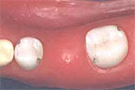

歯の削る量がとても少なくてすむ歯冠修復法

接着ブリッジでは歯を削る量が髪の毛1本分で通法の1/10程度で十分です

通法では隣在歯を大胆に全面全周にわたって削り,金属で被いかぶせるようになります。

咬む面や側面にご自身の歯を残せますので違和感ありません。噛み合わせの高さも変わりません。

咬む面を金属で被いかぶせるので多少なりとも噛み合わせが異なります。